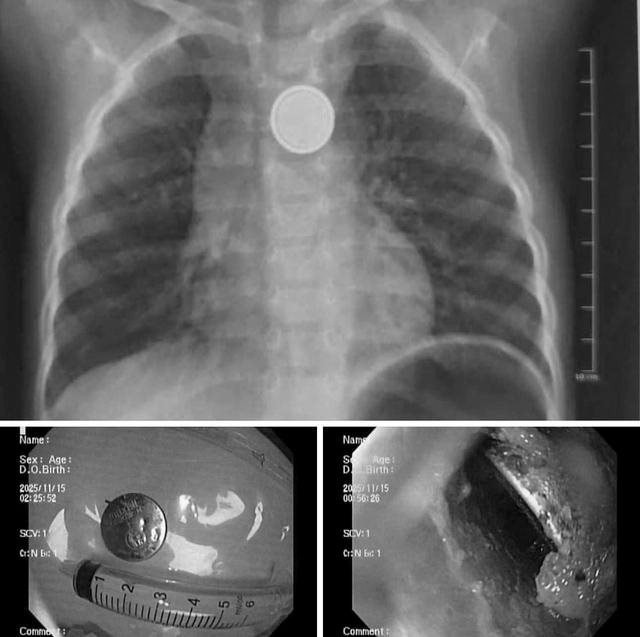

Kết quả X-quang cho thấy dị vật mắc lại ở thực quản. Các bác sĩ tiến hành nội soi cấp cứu và gắp thành công viên pin. Tuy nhiên, quan sát trực tiếp tại vị trí mắc cho thấy vùng thực quản đã bị ăn mòn và loét lớn - minh chứng pin cúc áo có thể gây tổn thương nặng nề chỉ trong thời gian rất ngắn, dù trẻ được đưa đến viện sớm.

Hình ảnh viên pin cúc trong thực quản bệnh nhi. Ảnh: Bệnh viện Nhi Hải Phòng

Theo ê-kíp điều trị, việc lấy dị vật kịp thời giúp hạn chế nguy cơ thủng thực quản, nhiễm trùng trung thất và các biến chứng nghiêm trọng khác có thể đe dọa tính mạng trẻ.

Hình ảnh dị vật là pin cúc áo trong thực quản trẻ. Ảnh: Bệnh viện Nhi Hải Phòng